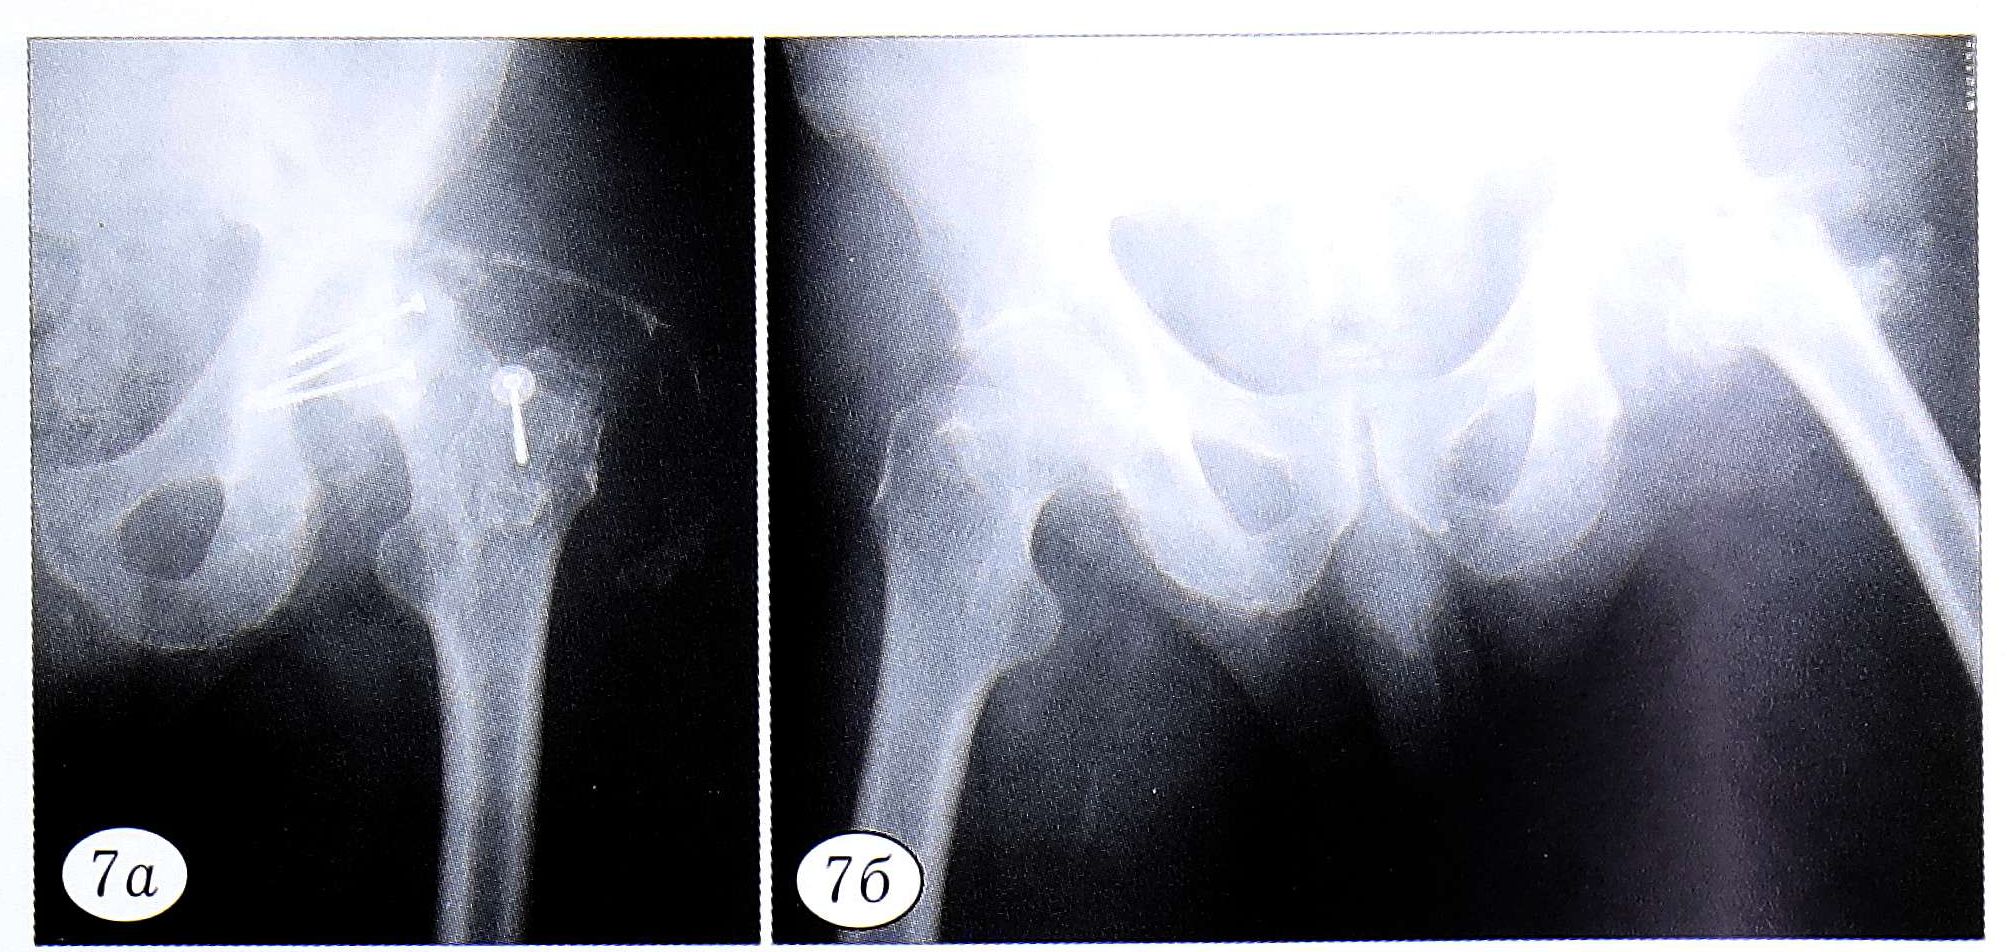

Занятия лечебной гимнастикой проводятся в положении пациента лежа на спине и сидя с отведенной ногой. Основными на этом этапе являются дыхательные упражнения в сочетании с элементами массажа грудной клетки. Они чередуются с упражнениями, направленными на укрепление мышц верхних конечностей, спины и здоровой нижней конечности, что обеспечивает подготовку больного к ходьбе при помощи костылей. Кроме того, назначаются изометрические упражнения для мышц оперированной конечности и щадящие пассивно-активные сгибания в коленном суставе (рис. 7 и 8, а). Начиная со 2-3-го дня после операции больному рекомендуется присаживаться в постели, используя балканскую раму и трапецию.

Рис. 7. Больной М. 52 лет. Остеомиелит проксимального отдела бедра и вертлужной впадины, развившийся после остеосинтеза винтами по поводу перелома заднего края вертлужной впадины. а — фистулограмма при поступлении; б — рентгенограмма через 30 дней после резекционной секвестрнекрэктомии костей, образующих тазобедренный сустав: на опиле проксимального отдела бедра видна выемка, выполненная для более плотного контакта с крышей вертлужной впадины.